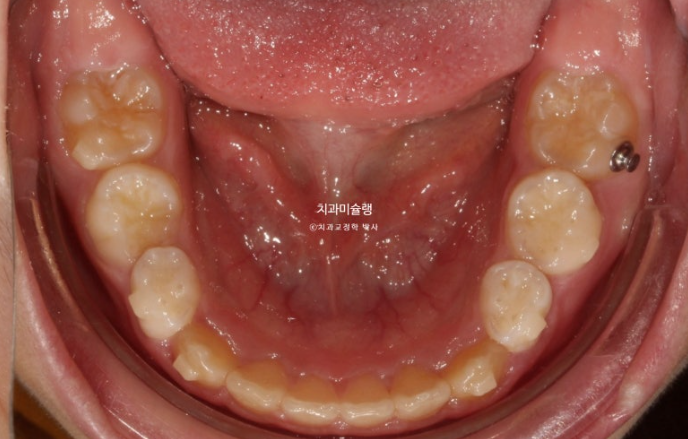

2년 전 교정치료를 위해 온 만 10세 어린이 입니다.

앞니가 하나 들려있고 깊게 물리는 과개교합이 있습니다.

중심선 불일치도 보입니다.

윗니 돌출이 측면에서 잘 보이네요.

영구치날 공간은 비교적 양호한 편입니다.

파란화살표 자리에 있어야할 작은어금니가 선천적 결손 상태입니다.

이런 경우 계승영구치가 없어 오래도록 남아있게될 잔존유치를 최대한 보존해서 쓰는 방법으로 치료를 합니다.